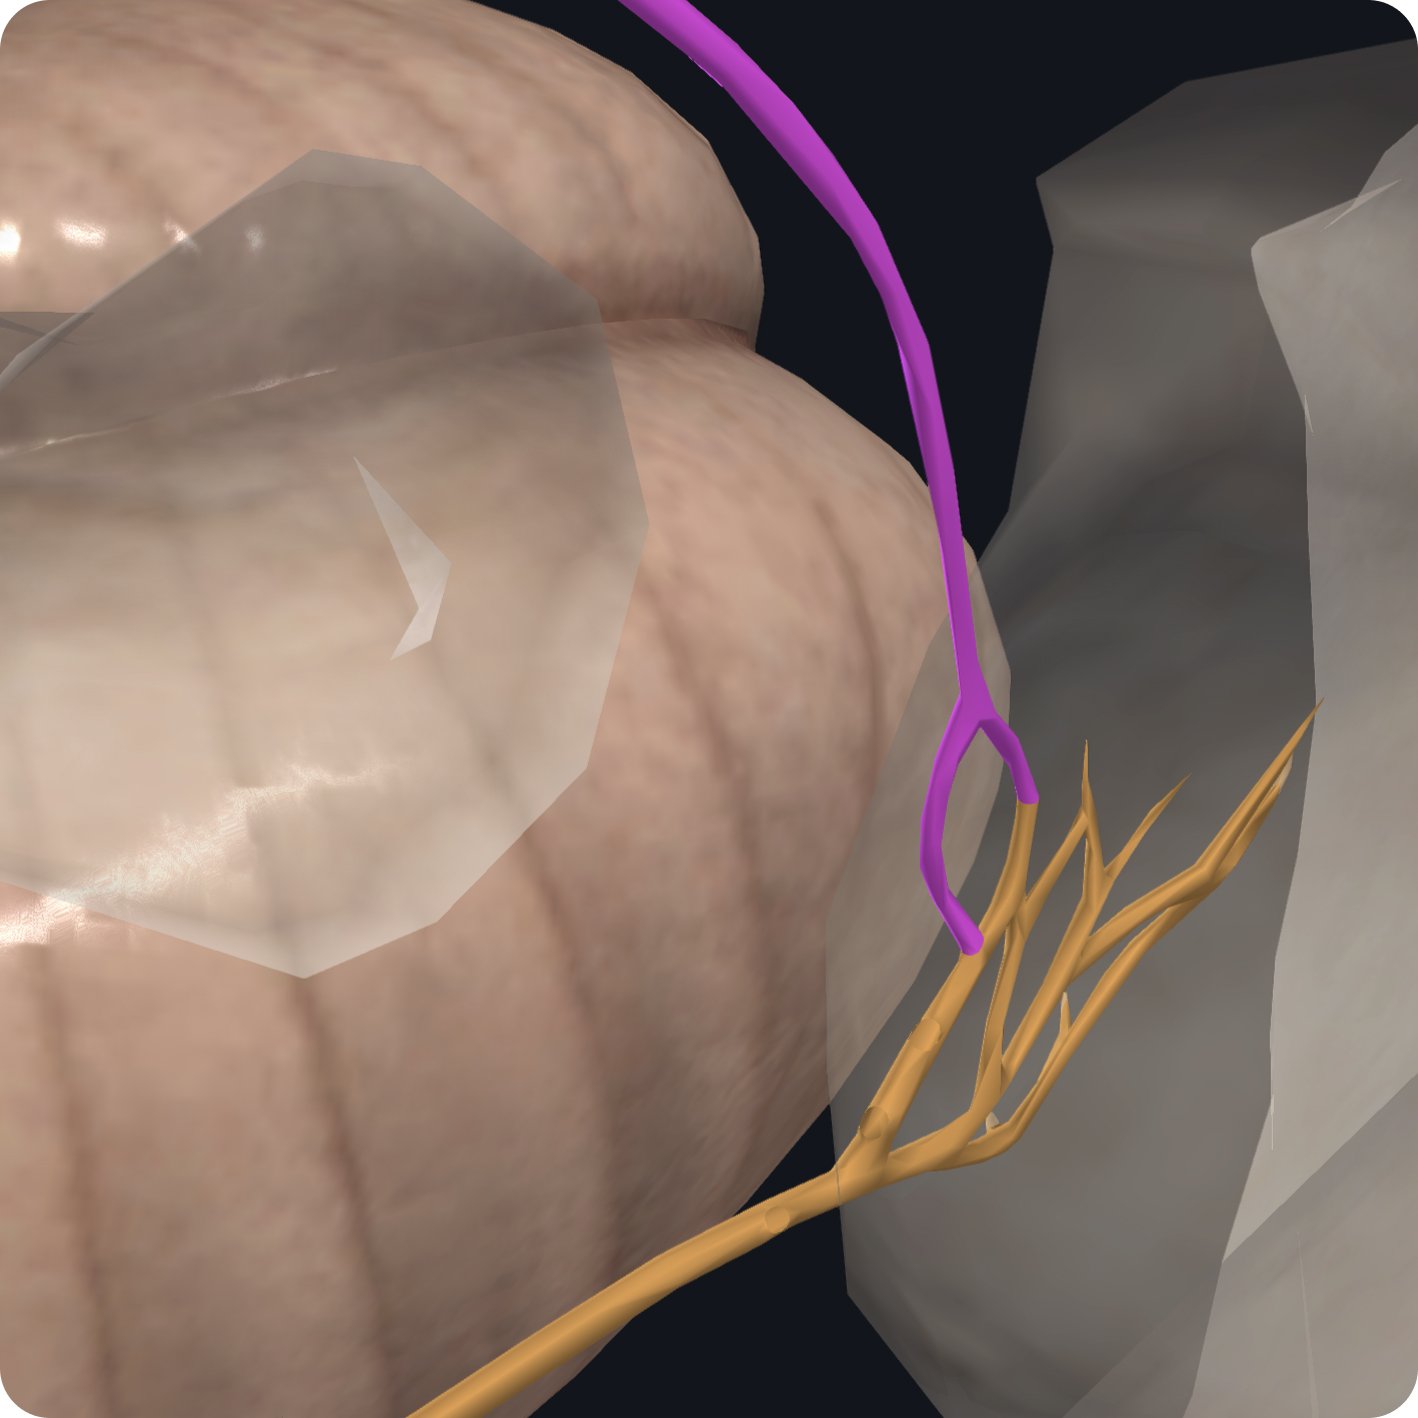

The remainder of the glossopharyngeal nerve runs inferior and anteriorly passing between the internal jugular vein and internal carotid artery.

Here, it gives off the second branch the carotid sinus nerve.

The carotid sinus nerve supplies the carotid sinus and carotid body.

The third branch of the glossopharyngeal nerve is the pharyngeal branch, which carries general visceral sensory fibers from the oropharynx and surrounding mucosal membranes.

It then unites with the vagus nerve and sympathetic trunk to form the pharyngeal plexus supplying the muscles of the pharynx and the soft palate.

The glossopharyngeal nerve gives off a fourth branch the stylopharyngeal branch which wraps around the stylopharyngeus muscle providing motor innervation to this muscle.